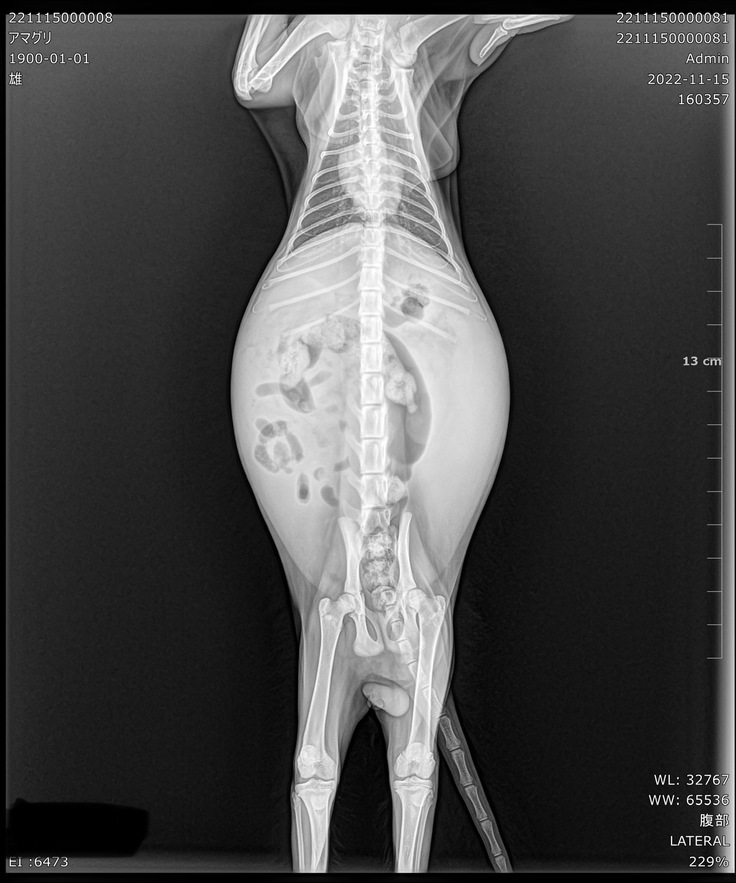

お腹が膨れ上がりおかしいと思い、近くの病院に行った所、膀胱炎の初期と診断され抗生物質と消炎剤の薬を10日分出され1日1回あげていましたが、一向によくならない為別の病院に行き血液検査をしてもらったところFIPの可能性があると診断されました。

私自身、FIPという病気自体は認識がありましたが、まさか自分の飼っている猫が診断されるとは思ってもおらず、どこの病院でも治療ができるわけではないみたいで、かかりつけの病院では治療ができないと言われました。

ウェットタイプは、胸膜や腹膜などの内臓を覆う膜に炎症が起きる「胸膜炎」や「腹膜炎」と、血管炎を特徴とします。これにより、腹水、胸水、心嚢水、陰嚢水が貯留します。胸水の貯留により、呼吸がしにくく苦しくなることがあります。ウェットタイプは進行が速く、診断後2週間〜1ヶ月程度で亡くなることもあります。

ドライタイプは、いろいろな臓器に肉芽腫を作るのが特徴です。肝臓に肉芽腫が作られると、肝機能が低下します。また、ドライタイプは、腎臓に肉芽腫を作ったり、糸球体腎炎を起こしたりすることで、腎機能の低下や腎腫大を引き起こします。眼にぶどう膜炎を引き起こすことがあり、虹彩の色を変化させることがあるので、眼の色が変わった時には注意が必要です。脳に炎症を起こし、神経症状を生じさせることもあります。

あまぐりは当時皮下注射治療中で、日本未承認の薬を84日間投与し続けなければいけませんでした。ただ未認可ということで保険適用外のため、非常に高額で、症状や体重によっても投薬量や金額が変わってきます。

無事病院に到着し検査と治療の為そのまま入院、手遅れになるといけないのでFIP治療、投薬を開始しました。